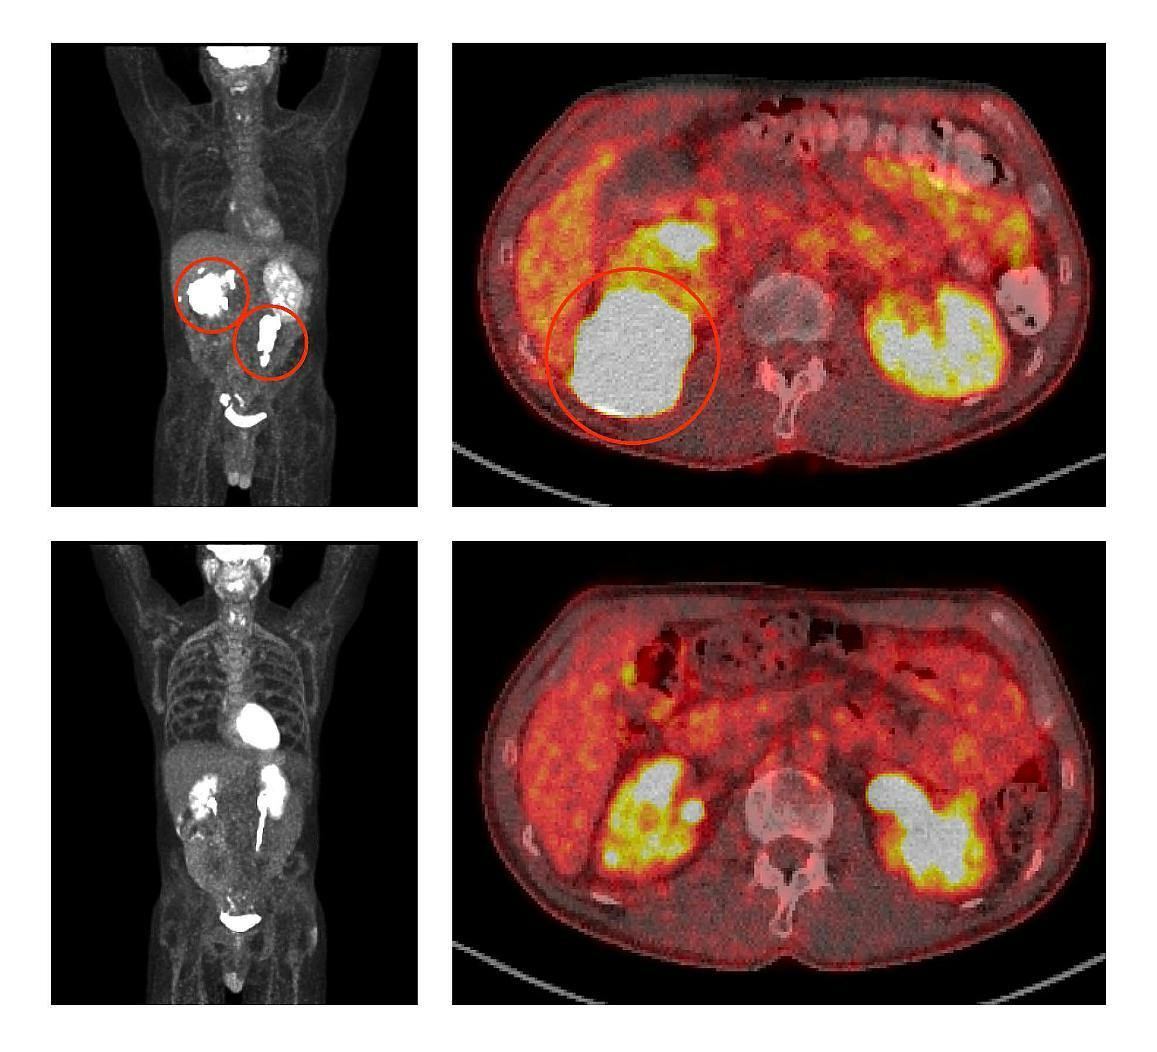

In a clinical trial at NIH’s National Cancer Institute, researchers tested the combination of venetoclax, ibrutinib, prednisone, obinutuzumab, and lenalidomide (called ViPOR) in 50 patients with DLBCL, the most common type of lymphoma. The treatment shrank tumors substantially in 26 of 48 (54%) evaluable patients, with 18 (38%) of those patients’ tumors disappearing entirely, known as a complete response. At two years, 36% of all patients were alive and 34% were free of disease. These benefits were seen mainly in people with two specific subtypes of DLBCL.

In the phase 1b/2 trial, 50 people with DLBCL that had relapsed or stopped responding to treatment were given six cycles of the ViPOR regimen. Responses to ViPOR varied by DLBCL subtype, with complete responses concentrated in two subtypes, including in 8 of 13 (62%) people with non-GCB DLBCL and 8 of 15 (53%) people with a form of GCB DLBCL known as high-grade B-cell lymphoma “double hit.”

At two years, people with non-GCB DLBCL and double-hit GCB DLBCL had higher rates of both progression-free and overall survival than other people in the study. Non-GCB DLBCL and double-hit GCB DLBCL are highly reliant on the survival mechanisms targeted by ViPOR, so it makes sense that they responded particularly well to the combination therapy. ViPOR also helped 6 of 20 (30%) patients whose lymphomas had not responded to or had come back after CAR T-cell therapy—the current standard of care for people with relapsed DLBCL—achieve lasting remissions.